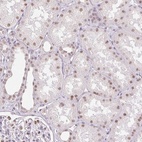

Immunohistochemical staining of human kidney shows moderate nuclear positivity in cells in tubules.